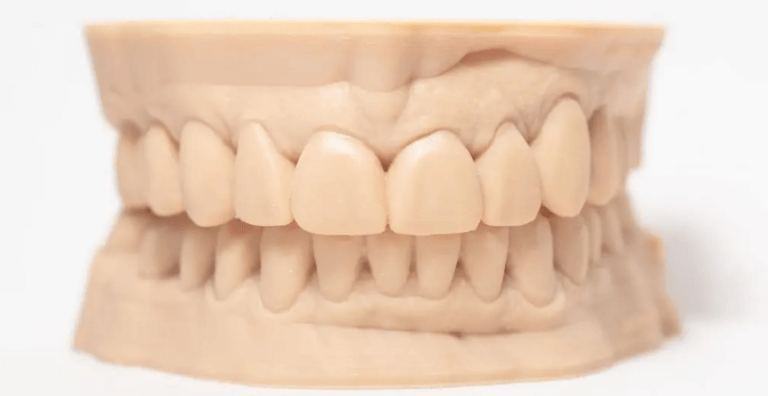

Kalite standartlarımız gereği, sadece klinik başarısı kanıtlanmış, sertifikalı ve güvenilir markaların materyallerini kullanıyoruz. Zirkonyum, E.max (lityum disilikat), hibrit seramikler, titanyum ve değerli metal alaşımları gibi geniş bir materyal yelpazesine sahibiz. Özel bir materyal veya implant markası talebiniz olursa, lütfen vaka öncesinde bizimle iletişime geçerek stok ve uyumluluk bilgisi alınız.